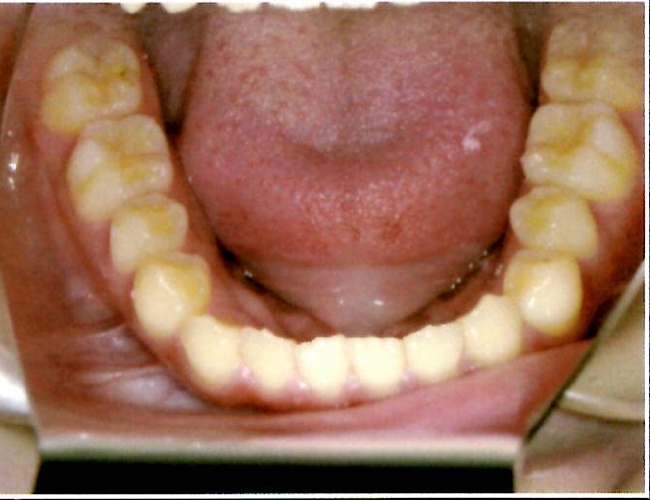

| 主訴・治療前の状態 | 下顎前歯部に叢生(ガタガタ)があり、歯ブラシが届きにくく清掃性に問題がありました。また、見た目も気にされていました。 |

| 治療内容 | 下顎前歯を1本のみ抜歯し、歯列を整えました。治療に際しては、ブラックトライアングル(歯と歯の間の歯茎部分に三角形の隙間ができること)が生じる可能性について事前に説明し、患者様にご了承いただいた上で治療を開始しました。 |

| 治療結果 | 予定通りの仕上がりとなり、事前説明の通りブラックトライアングルは生じましたが、患者様には十分ご理解いただいており、満足度の高い結果となりました。 |